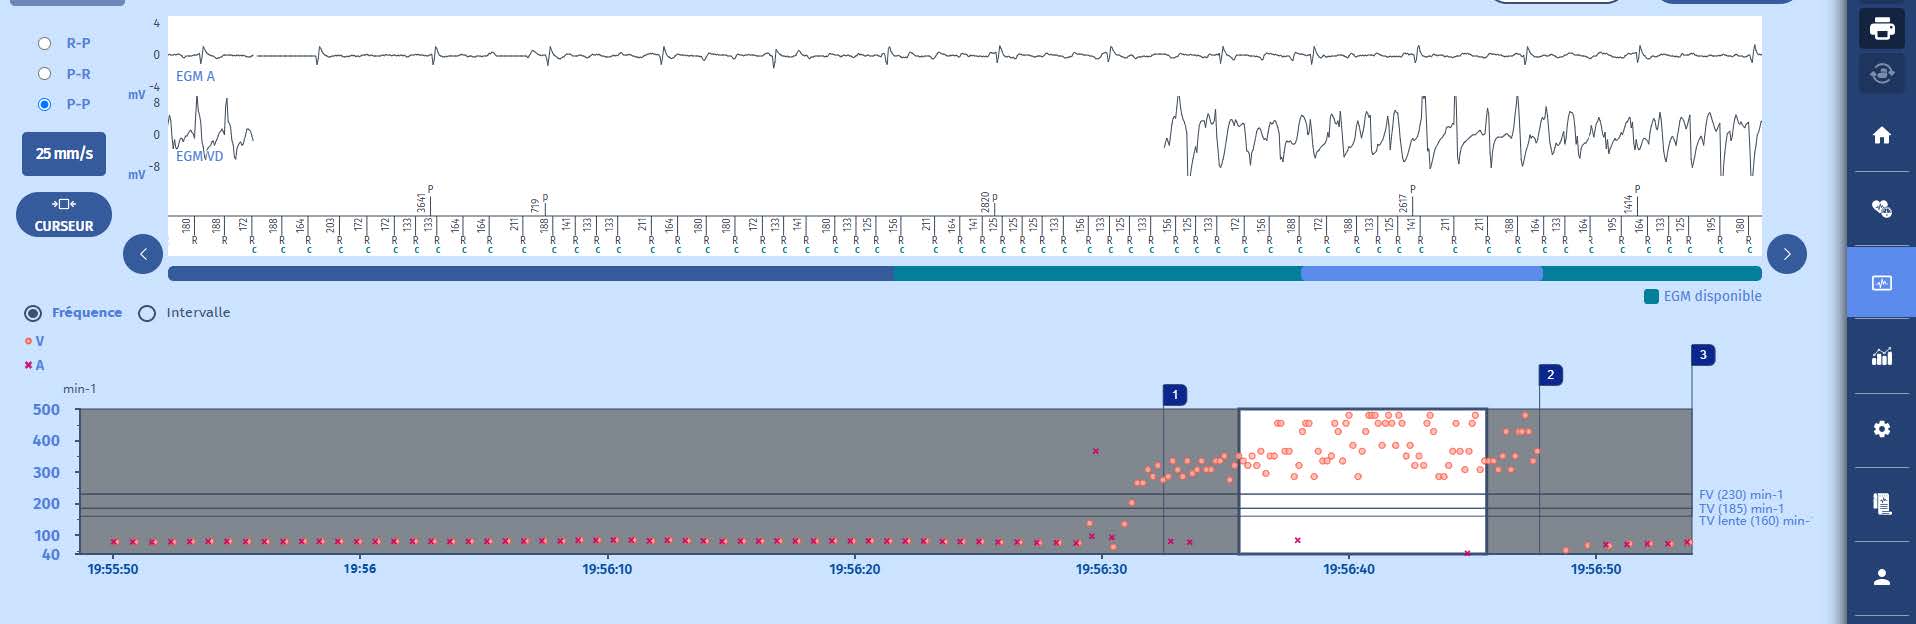

Voici l'écran, remarquez qu'il y a eu un épisode avec des thérapies ;

Tachogramme

Apparition d'une tachycardie très rapide dans la zone de FV avec une grande variabilité du cycle, pour laquelle un diagnostic rapide de FV est posé avec l'administration d'un choc rétablissant le rythme lent.